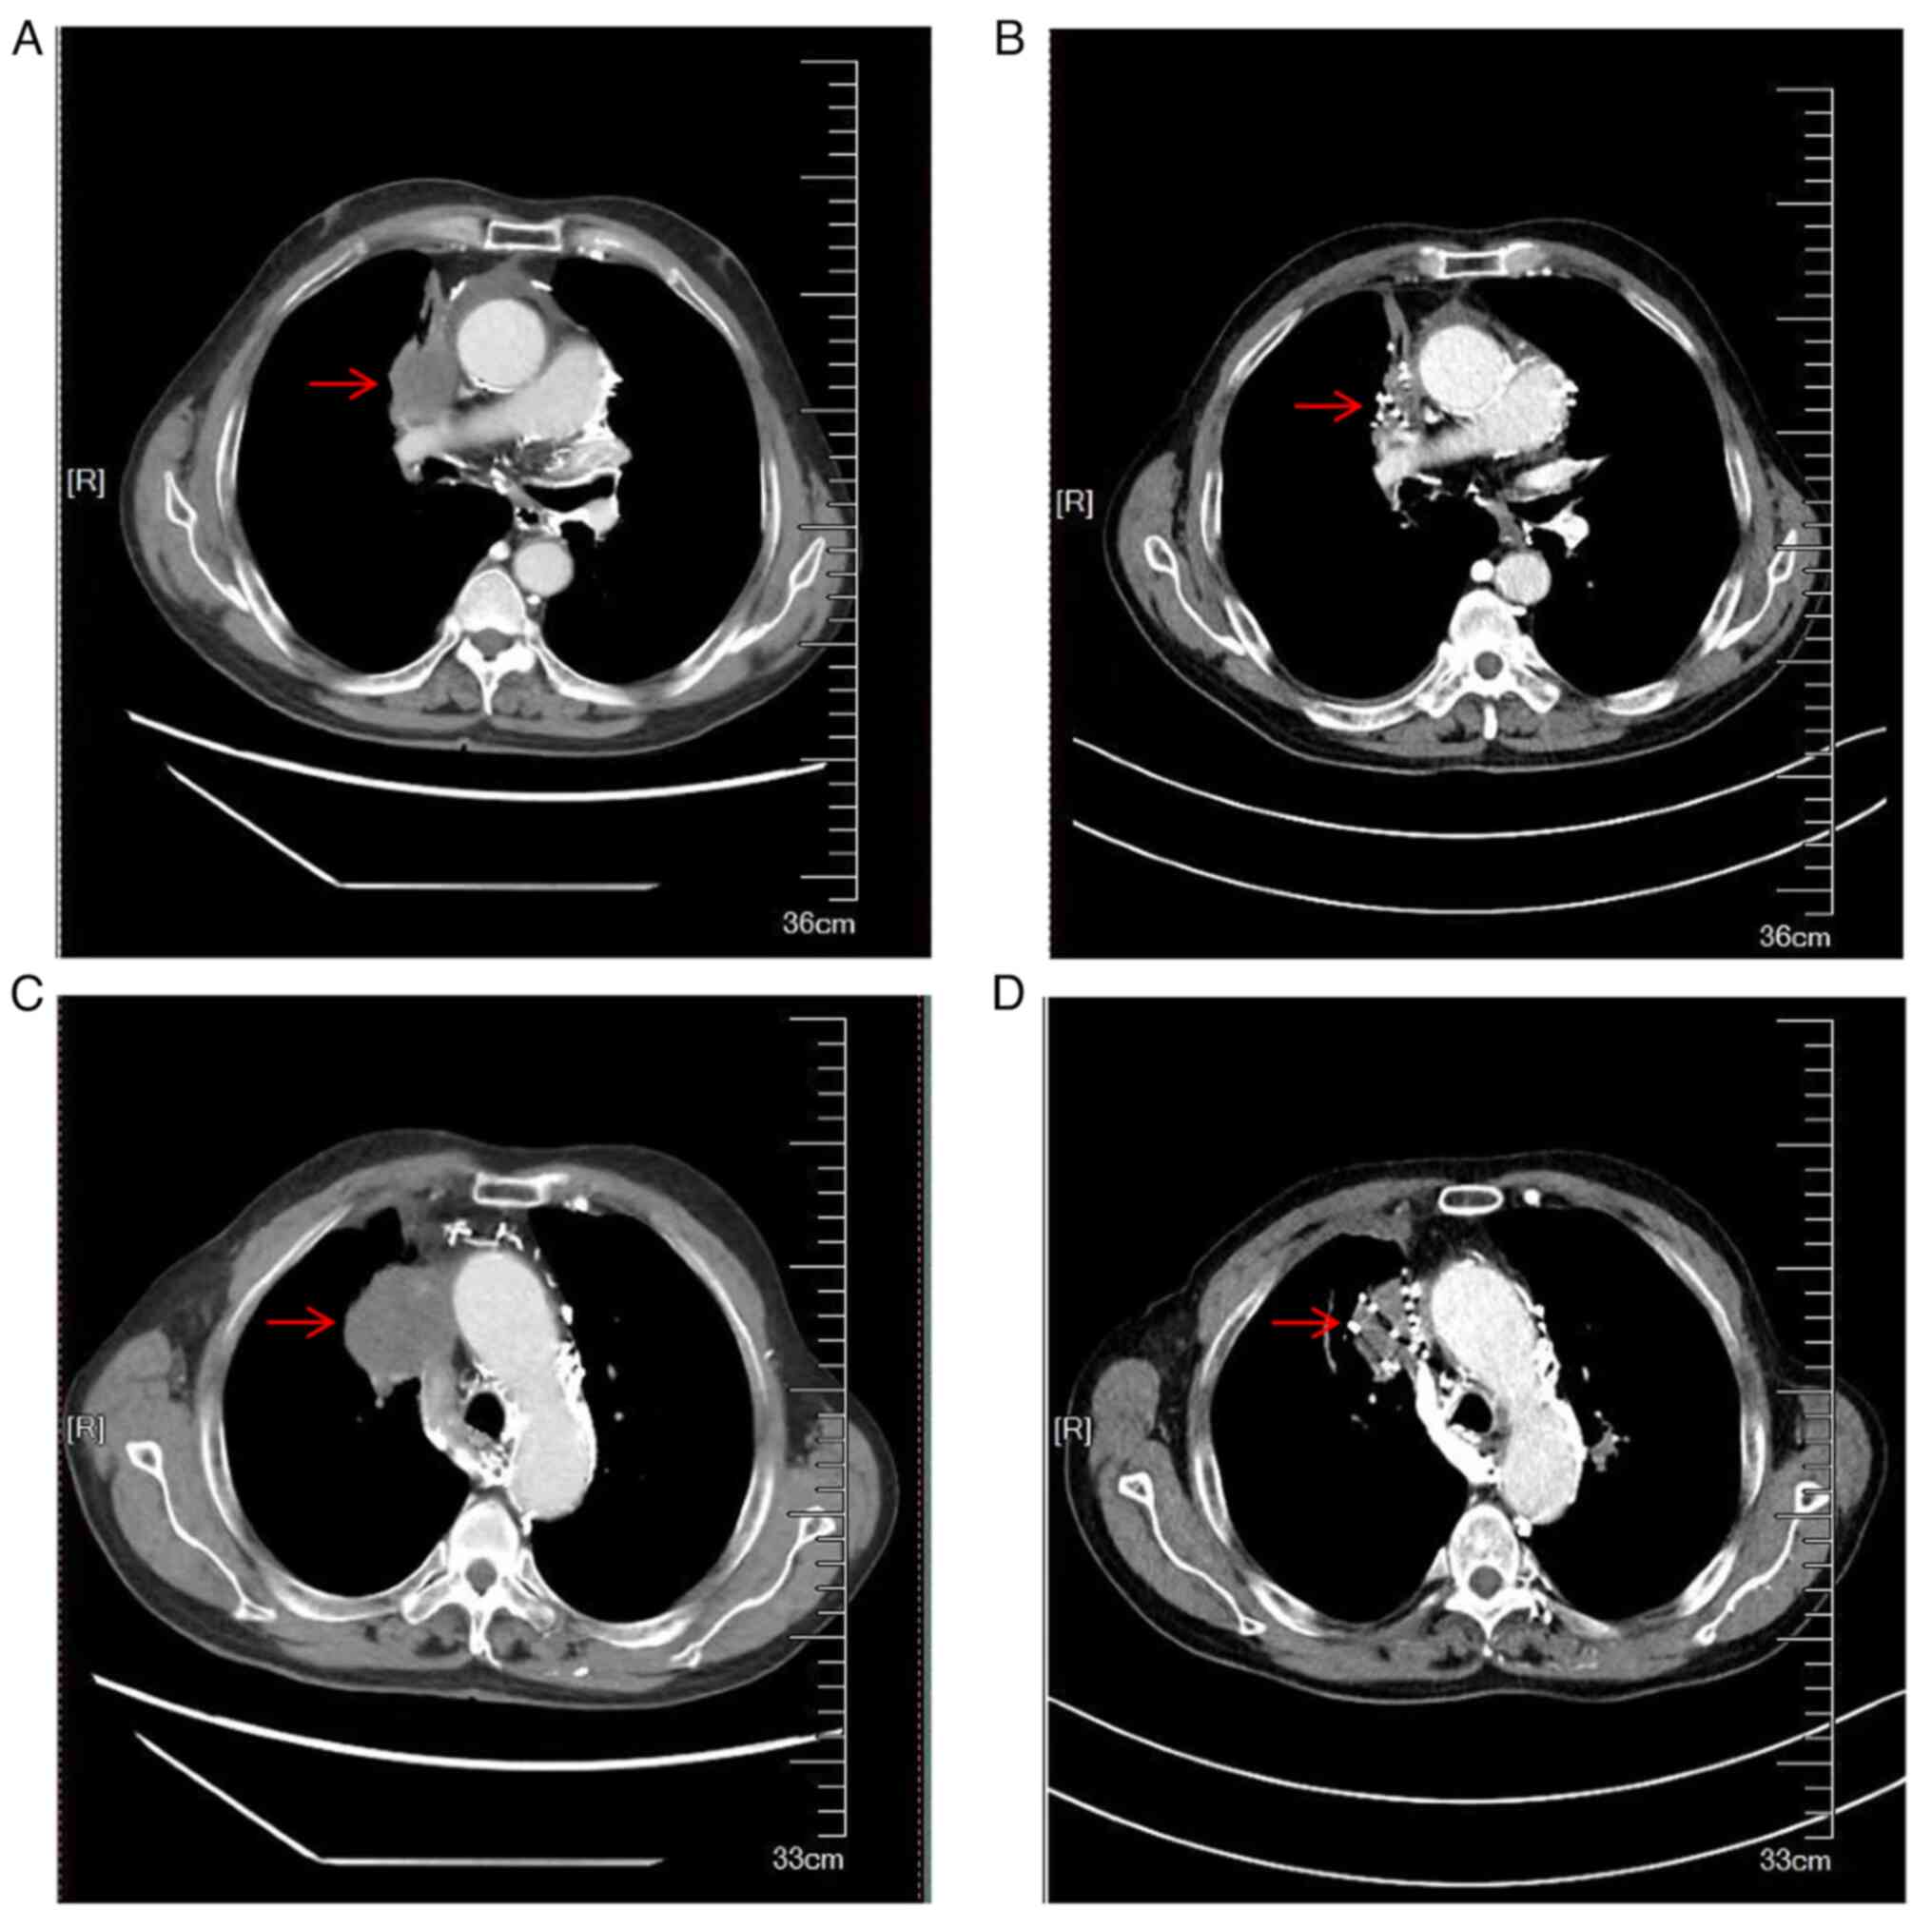

Physical examination revealed noticeable facial and neck bruising and edema, jugular vein enlargement, swelling in both upper limbs, and superficial varicose veins in the upper abdomen and anterior chest wall. Enhanced CT of the chest indicated that the tumor had invaded the right upper lobe of the lung and the superior vena cava (Fig. 1). Moreover, multiple dilated vessels were observed in the mediastinum and the patient developed emphysema. The patient was positive for the cancer markers squamous cell cancer-related antigen and cytokeratin 19, as well as neuron-specific carcinoma markers were normal. The mutation status of epidermal growth factor receptor and anaplastic lymphoma kinase fusion genes was analyzed by blood genetic test; the patient did not harbor the anaplastic lymphoma kinase gene fusion or epidermal growth factor receptor mutations. After a discussion with the multidisciplinary tumor board, I125 seed brachytherapy and radiotherapy were recommended, and the patient provided their consent for I125 brachytherapy.

Figure 1.

Comparison of preoperative and postoperative dose-volume histogram images. (A) preoperative dose-volume histogram images; (B) is postoperative dose-volume histogram images.

After an 8-month follow-up period, it was observed that the tumor had shrunk (Fig. 4). In addition, the symptoms of superior vena cava compression were notably relieved, facial edema had almost completely disappeared, there were fewer tortuous blood vessels in the front chest wall, and the severity of cough and expectoration was lesser than that observed before brachytherapy. Despite this, the patient experienced systemic tumor progression, pneumonia and respiratory failure, which eventually led to their death 8 months after brachytherapy.

Figure 4.

Comparison of CT images before surgery and 2 months after surgery. (A) is enhanced chest CT images of the patient's progress after comprehensive treatment; (B) is CT images of different layers of the tumor; (C) is the CT image of the same level 2 months after the implantation of particle (A and D) is the CT image of the same level 2 months after the operation of (B). Visible shrinkage of the tumor (arrow).